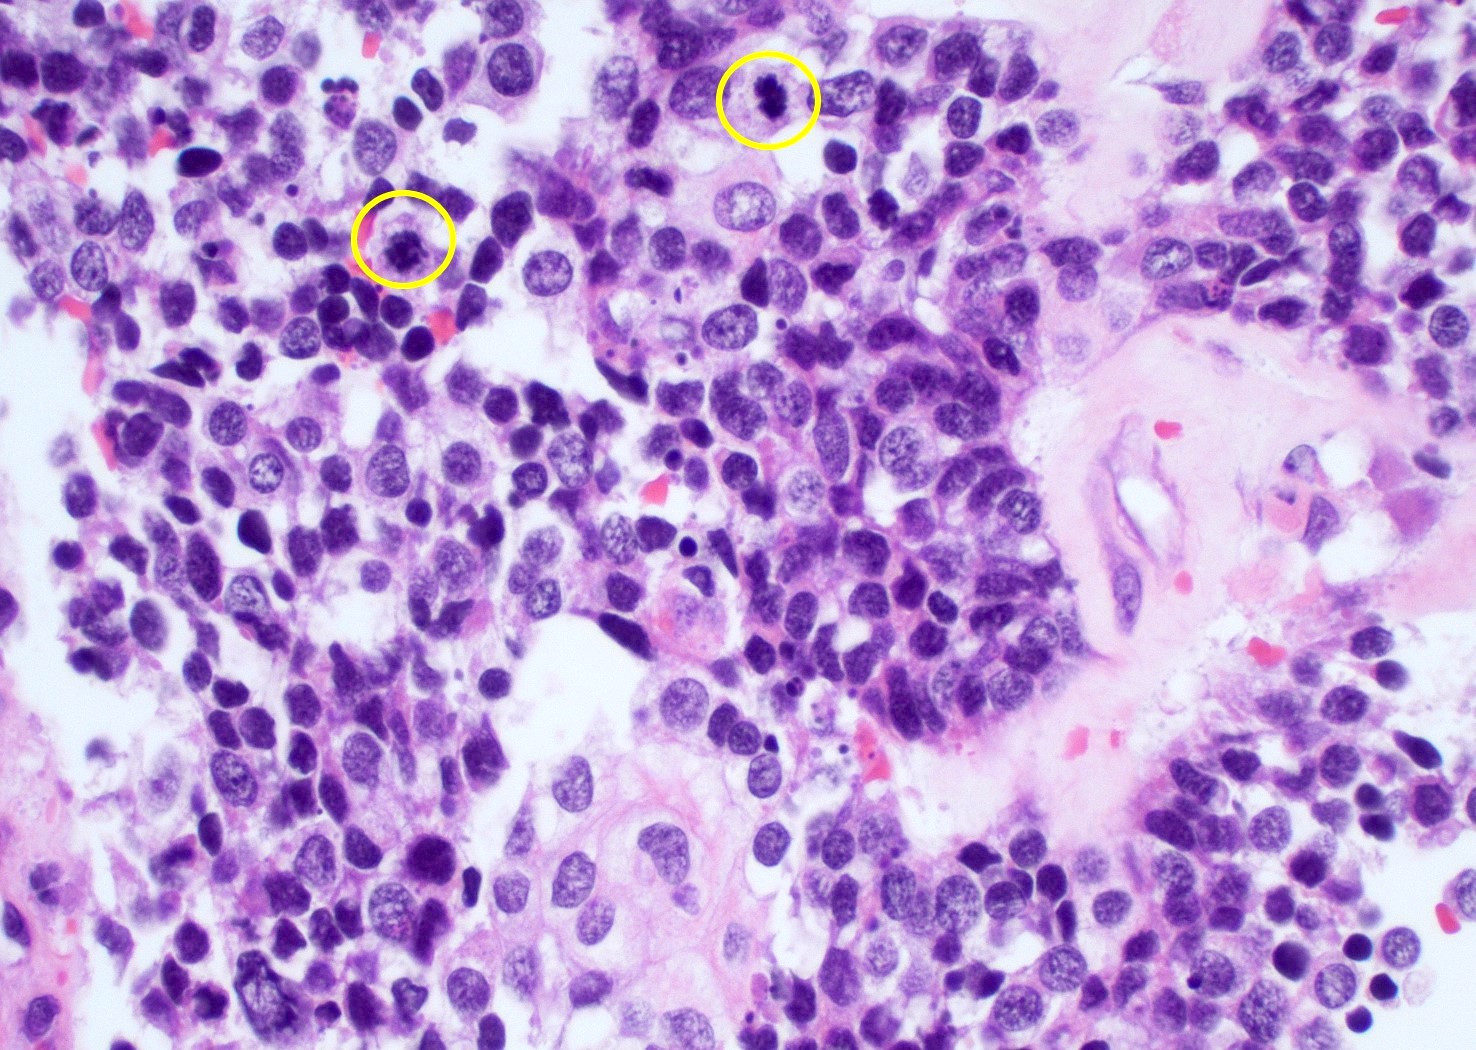

Microscopic (histologic) description

- Infiltrating, hypercellular astrocytic neoplasm often with hyperchromatic, elongated nuclei and irregular nuclear membranes

- Typically mitotically active, though not required if molecular criteria are met

- Microvascular proliferation or necrosis is required for a histologic diagnosis of GBM

- Variable cell morphology: undifferentiated / primitive neuronal cells, astrocytic, gemistocytic, oligodendroglial-like, small cell, lipidized, granular, epithelioid, giant cells, mesenchymal metaplasia and epithelial metaplasia

- Primitive neuronal cells (embryonal): markedly increased cellularity composed of cells with high N/C ratio, brisk mitotic activity with apoptotic bodies, nuclear molding, sometimes with neuroblastic rosettes

- Typically has conventional infiltrating astrocytic component, which is morphologically distinct

- Loss of glial markers, expression of neuronal markers (synaptophysin)

- Higher risk of CSF dissemination but similar survivals as classic GBM

- Associated with MYC amplifications

- Primitive neuronal cells (embryonal): markedly increased cellularity composed of cells with high N/C ratio, brisk mitotic activity with apoptotic bodies, nuclear molding, sometimes with neuroblastic rosettes

Microscopic (histologic) images

Contributed by Bharat Ramlal, M.D. and Meaghan Morris, M.D., Ph.D.

C. Primitive neuronal component. Glioblastomas with a primitive neuronal component have an increased risk of CSF spread and potential for distant metastasis in rare case reports. As such, this particular morphologic finding may be important to bring to the attention of the clinical team. A primitive neuronal component in glioblastoma can be diagnosed by identifying a morphologically distinct area with high cellularity, high mitotic activity, loss of expression of glial markers and expression of neuronal markers such as synaptophysin.